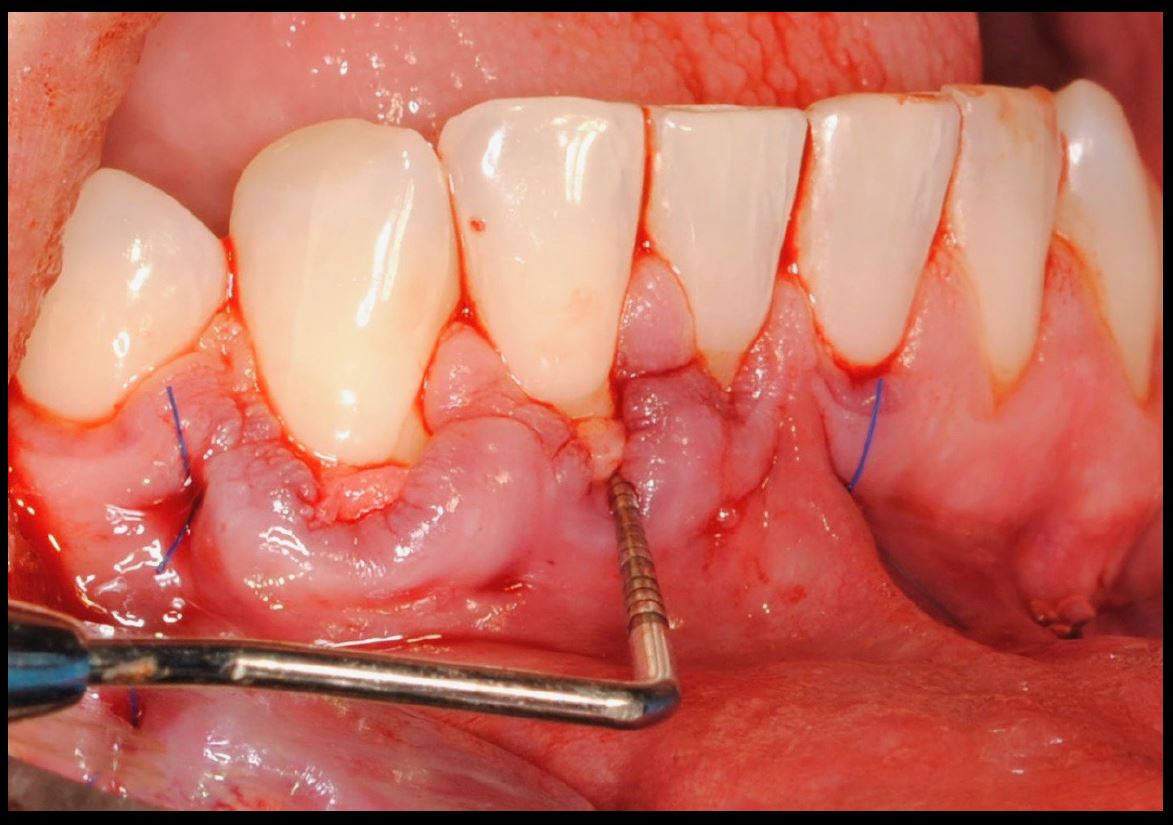

Objetivos periodontales: Mediante ingerto de tejido conectivo subepitelial de paladar con técnica de tunelización.

- Injerto de tejido conectivo libre desepitelizado de paladar + Tunelización

Fotografías del proceso: